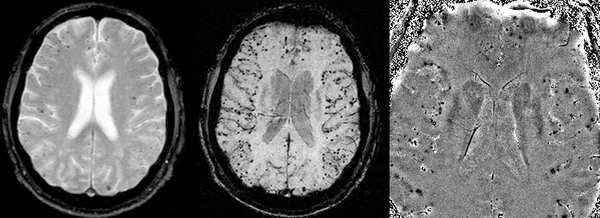

Магнитно-резонансная томография является ключевым методом диагностики ЦАА, так как позволяет выявить характерные для этого заболевания множественные корковые и корково-субкортикальные кровоизлияния. Наибольшей чувствительностью в обнаружении даже мелких и клинически бессимптомных кровоизлияний обладает режим Т2 градиентного эхо, который визуализирует следы гемосидерина в виде множественных точечных гипоинтенсивных очагов, рассеянных в коре и на границе с белым веществом[1][5].